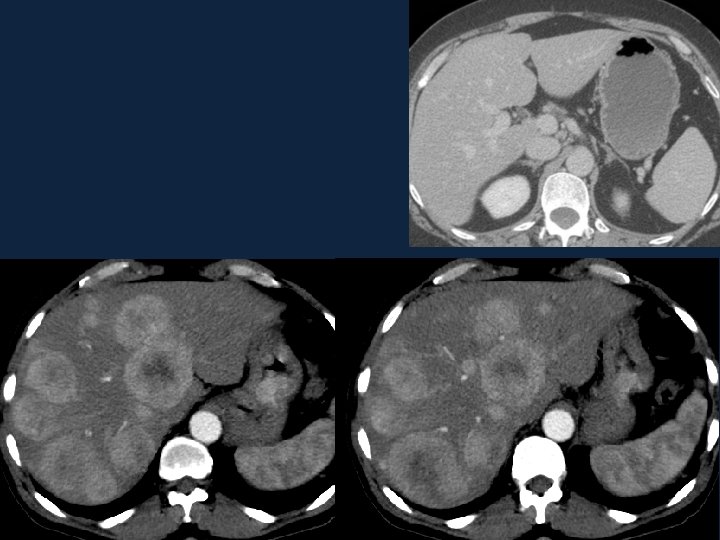

• Above: arterial phase showing hypervascular FNH • Middle: portal venous phase showing hypovascular metastases • Down: equilibrium phase showing relatively dense cholangiocarcinoma

• History : A 40 year old male came with abdominal pain

• Technique Triphasic contrast enhanced CT was performed for the chest, abdomen and pelvis.

• Diagnosis Carcinoid tumor of the stomach with hypervascular metastasis to the liver